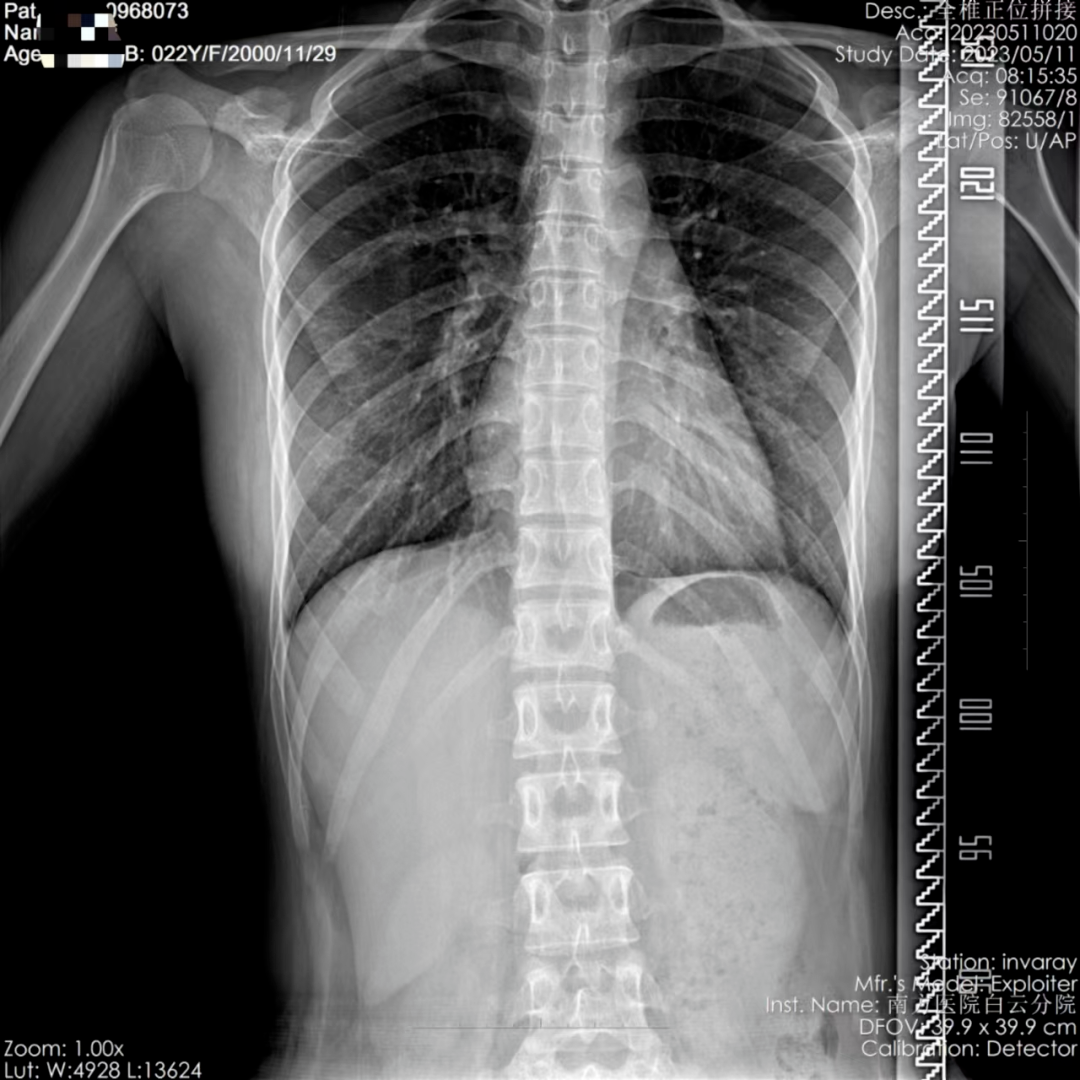

医院高度重视,为患者开通绿色通道,医务部、药学部等部门、科室积极配合,第一时间采购诺西那生钠注射液。术前,在白云脑血管病医院潘速跃院长及刘晓加主任的支持下,神经医学科蒋海山教授、周俊球主治医师、谢文艺住院医师对患者进行详细体格检查并完善全脊柱MRI、CT等检验检查,同时请神经康复中心梁井凤医师详细地评估患者运动功能。在与家属充分沟通、交代病情后,制定了详细的腰椎穿刺+诺西那生钠注射液鞘内注射方案。

图2.来源于南方医院白云分院